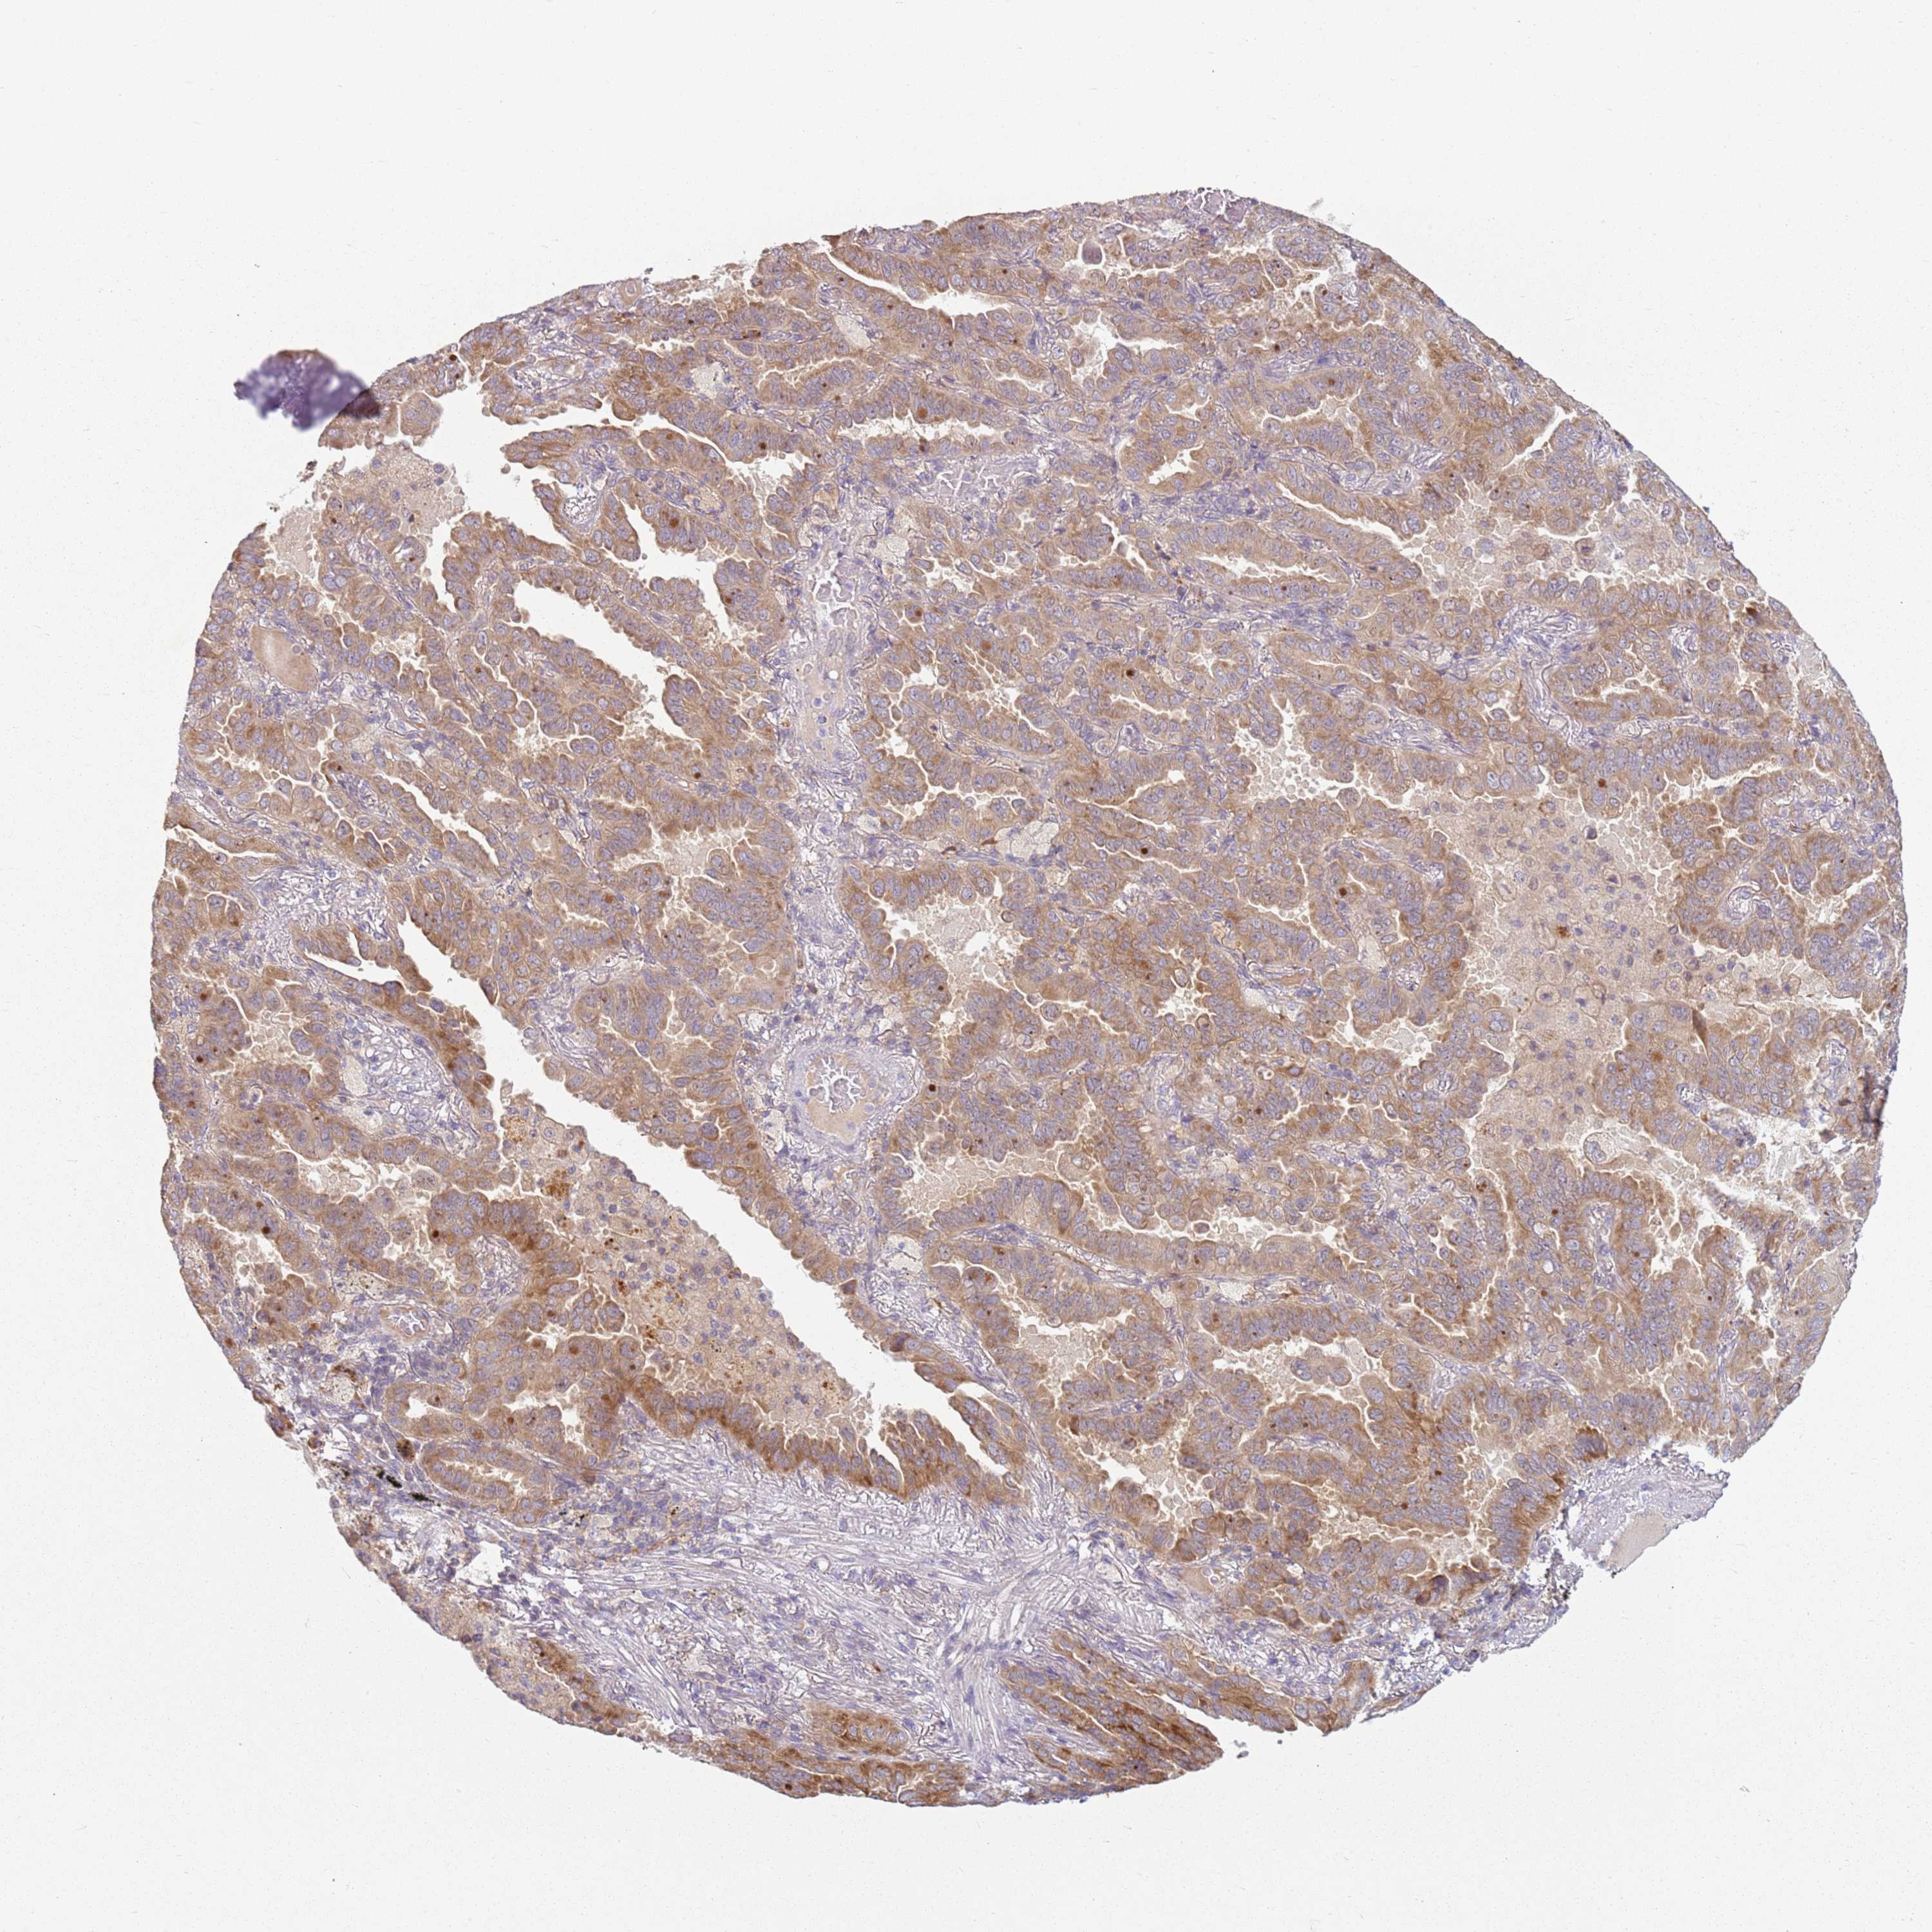

LUNG SQUAMOUS CELL CARCINOMA (TCGA) - Interactive survival scatter ploti

The Survival Scatter plot shows the clinical status (i.e. dead or alive) for all individuals in the patient cohort, based on the same data that underlies the corresponding Kaplan-Meier plots. Patients that are alive at last time for follow-up are shown in blue and patients who have died during the study are shown in red.

The x-axis shows the expression levels (FPKM) of the investigated gene in the tumor tissue at the time of diagnosis. The y-axis shows the follow-up time after diagnosis (years). Both axes are complimented with kernel density curves demonstrating the data density over the axes. The top density plot shows the expression levels (FPKM) distribution among dead (red) and alive patients (blue). The right density plot shows the data density of the survived years of dead patients with high and low expression levels respectively, stratified using the cutoff indicated by the vertical dashed line through the Survival Scatter plot. This cutoff is automatically defined based on the FPKM cutoff that minimizes the p-score. The cutoff can be changed by dragging the vertical line or by entering a cutoff value in the square labeled "Current cut-off".

Under the Survival Scatter plot the p-score landscape (black curve; left axis) is shown together with dead median separation (red curve; right axis). Dead median separation is the difference in median mRNA expression between patients who have died with high and low expression, respectively. It is calculated as follows: median FPKM expression of dead patients with high expression - median FPKM expression of dead patients with low expression. This is intended to aid the user in visually exploring custom cutoffs and the associated p-scores and dead median separation.

Individual patient data is displayed and can be filtered by clicking on one or more of the category buttons on the top of the page. Categories describing expression level and patient information include: high, low, alive, dead, female, male and tumor stages. The scale of the x-axis can be toggled between linear and log-scale by clicking on the "x log" button. Mouse-over function shows TCGA ID, patient information and mRNA expression (FPKM) for each patient.

& Survival analysisi

Kaplan-Meier plots summarize results from analysis of correlation between mRNA expression level and patient survival. Patients were divided based on level of expression into one of the two groups "low" (under cut off) or "high" (over cut off). X-axis shows time for survival (years) and y-axis shows the probability of survival, where 1.0 corresponds to 100 percent.

RPS28 is not prognostic in Lung Squamous Cell Carcinoma (TCGA)

Stage:

Survival analysis

Current cut offi

Current cut-off shows the cut-off (FPKM) currently selected. It may be changed manually. When the current cut-off is changed, the vertical dashed line indicating cut-off, the interactive survival scatter plot and the Kaplan-Meier curve will be automatically adjusted to show results accordingly.

:

Best expression cut offi

Based on the FPKM value of each gene, patients were classified into two groups and association between prognosis (survival) and gene expression (FPKM) was examined. The best expression cut-off refers the FPKM value that yields maximal difference with regard to survival between the two groups at the lowest log-rank P-value. Best expression cut-off was selected based on survival analysis .

When clicking on this number, the vertical dashed line indicating cut-off, the interactive survival plot, and the Kaplan-Meier curve will be adjusted to show results based on the best expression cut-off.

: 177.61

Median expressioni

Median expression refers to the median FPKM value calculated based on the gene expression (FPKM) data from all patients in this dataset. When clicking on this number, the vertical dashed line indicating cut-off, the interactive survival plot, and the Kaplan-Meier curve will be adjusted to show results based on the median expression.

: N/A

Median follow up timei

Median follow up time refers to the median time (years) after diagnosis with this type of cancer, based on clinical data from all patients in this dataset.

P scorei

Log-rank P value for Kaplan-Meier plot showing results from analysis of correlation between mRNA expression level and patient survival.

N/A

5-year survival highi

5-year survival for patients with higher expression than the expression cutoff.

For melanoma and glioma, 3-year survival is shown.

5-year survival lowi

5-year survival for patients with lower expression than the expression cutoff.

TCGA RNA samplesi

RNA-seq data is reported as average FPKM (number Fragments Per Kilobase of exon per Million reads), generated by the The Cancer Genome Atlas (TCGA) .

Normal distribution across the dataset is visualized with box plots, shown as median and 25th and 75th percentiles. Points are displayed as outliers if they are above or below 1.5 times the interquartile range. FPKM values of the individual samples are presented next to the box plot.

Average pTPM 199.5

Number of samples 489